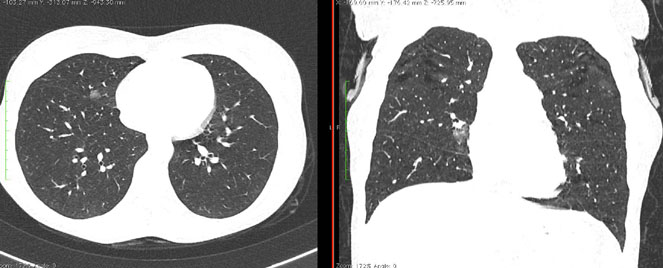

4.3. ЛУЧЕВАЯ ДИАГНОСТИКА COVID-19

Методы лучевой диагностики применяют для выявления COVID-19 пневмоний, их осложнений, дифференциальной диагностики с другими заболеваниями легких, а также для определения степени выраженности и динамики изменений, оценки эффективности проводимой терапии.

К методам лучевой диагностики патологии ОГК пациентов с предполагаемой/установленной COVID-19 пневмонией относят:

- Обзорную рентгенографию легких (РГ),

- Компьютерную томографию легких (КТ),

- Ультразвуковое исследование легких и плевральных полостей (УЗИ).

Стандартная РГ имеет низкую чувствительность в выявлении начальных изменений в первые дни заболевания и не может применяться для ранней диагностики. Информативность РГ повышается с увеличением длительности течения пневмонии. Рентгенография с использованием передвижных (палатных) аппаратов является основным методом лучевой диагностики патологии ОГК в отделениях реанимации и интенсивной терапии (ОРИТ). Применение передвижного (палатного) аппарата оправдано и для проведения обычных РГ исследований в рентгеновском кабинете. В стационарных условиях относительным преимуществом РГ в сравнении с КТ являются большая пропускная способность. Метод позволяет уверенно выявлять тяжелые формы пневмоний и отек легких различной природы, которые требуют госпитализации, в том числе направления в ОРИТ.

КТ имеет высокую чувствительность в выявлении изменений в легких, характерных для COVID-19. Применение КТ целесообразно для первичной оценки состояния ОГК у пациентов с тяжелыми прогрессирующими формами заболевания, а также для дифференциальной диагностики выявленных изменений и оценки динамики процесса. КТ позволяет выявить характерные изменения в легких у пациентов с COVID-19 еще до появления положительных лабораторных тестов на инфекцию с помощью МАНК. В то же время, КТ выявляет изменения легких у значительного числа пациентов с бессимптомной и легкой формами заболевания, которым не требуется госпитализация. Результаты КТ в этих случаях не влияют на тактику лечения и прогноз заболевания при наличии лабораторного подтверждения COVID-19. Поэтому массовое применение КТ для скрининга асимптомных и легких форм болезни не рекомендуется.